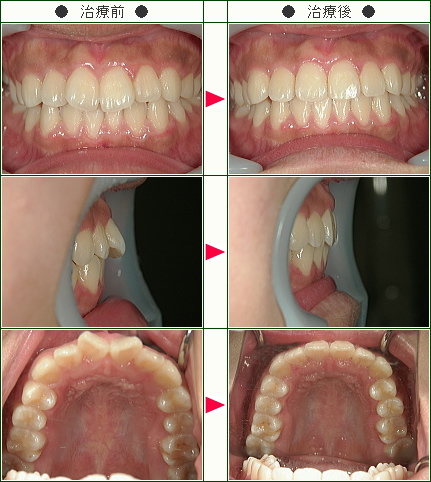

☆出っ歯矯正症例(A・H様 17歳 女性)

治療解説

主訴は前歯の前突感(出っ歯)の改善です。

まずはワイヤーを使用して右上のデコボコを改善していきます。

ワイヤーの使用期間が約3か月で、マウスピースを3か月使用して歯並びを内側に傾斜して治療していきました。

トータルでの治療期間は6ヵ月で、調整料金を含めたトータルの治療費は29万円です。

上側だけの部分矯正では、噛み合わせは変わりませんので、見た目の改善だけの審美治療になります。

部分矯正において、ワイヤーでデコボコを改善するだけだと、矯正前よりも少しだけ前方に出てしまうため、歯の隣接面を少し削ることで前歯の前突感を改善していきます。

どこまで前歯を中に入れたいかで、隣接面を削る量は患者様の判断で決まります。

歯を削らないでデコボコを治すだけですと、デコボコのある上の左右の1番目と上の2番目の間にブラックトライアングルという隙間が残るために、ブラックトライアングルを減らすためにもその部分の隣接面を削ってブラックトライアングルを改善していきます。